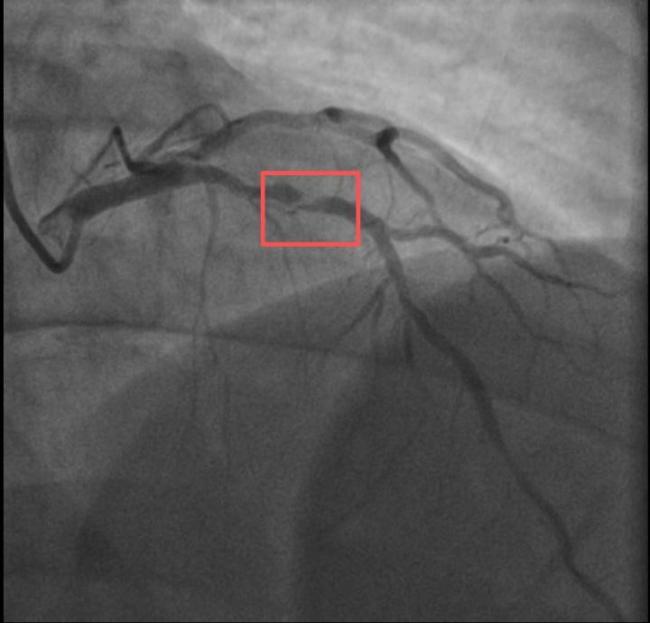

男子打10分钟羽毛球后心梗 剧烈运动成诱因

两个38岁的宝爸同一天因为急性心梗被送进医院,且都发生在剧烈运动后。一位陪孩子打了10分钟羽毛球,另一位陪孩子爬了一次山。这两位父亲的情况引发了人们的关注。孙先生是一位羽毛球教练,身高173cm,体重约90KG

03-26